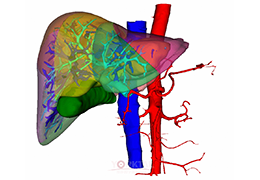

成像智能。

Eclipse 成像智能功能提供强大的处理能力和最佳质量的影像,同时减少质量错误并提高剂量效率。

凭借 AI、专有算法和先进的影像处理能力,提供出色的影像质量和无与伦比的诊断信心。